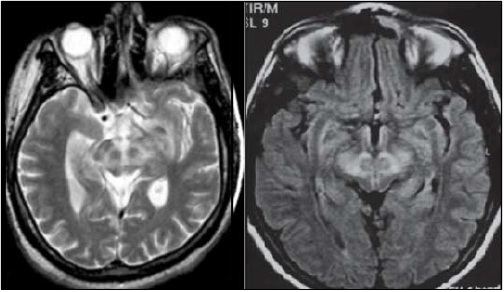

(Disponível em: https://cachorroidiota.files.wordpress.com/2012/08/2.png e Barra FR, Gonçalves FG, Matos VL, Jovem CL, Mendonça JLF, Amaral LLF, delCarpio-O’Donovan R. Sinais em neurorradiologia – Parte 2. Radiol Bras. 2011 Mar/Abr;44(2):129–133.)

Qual a patologia mais comumente relacionada ao achado nas imagens anteriores?